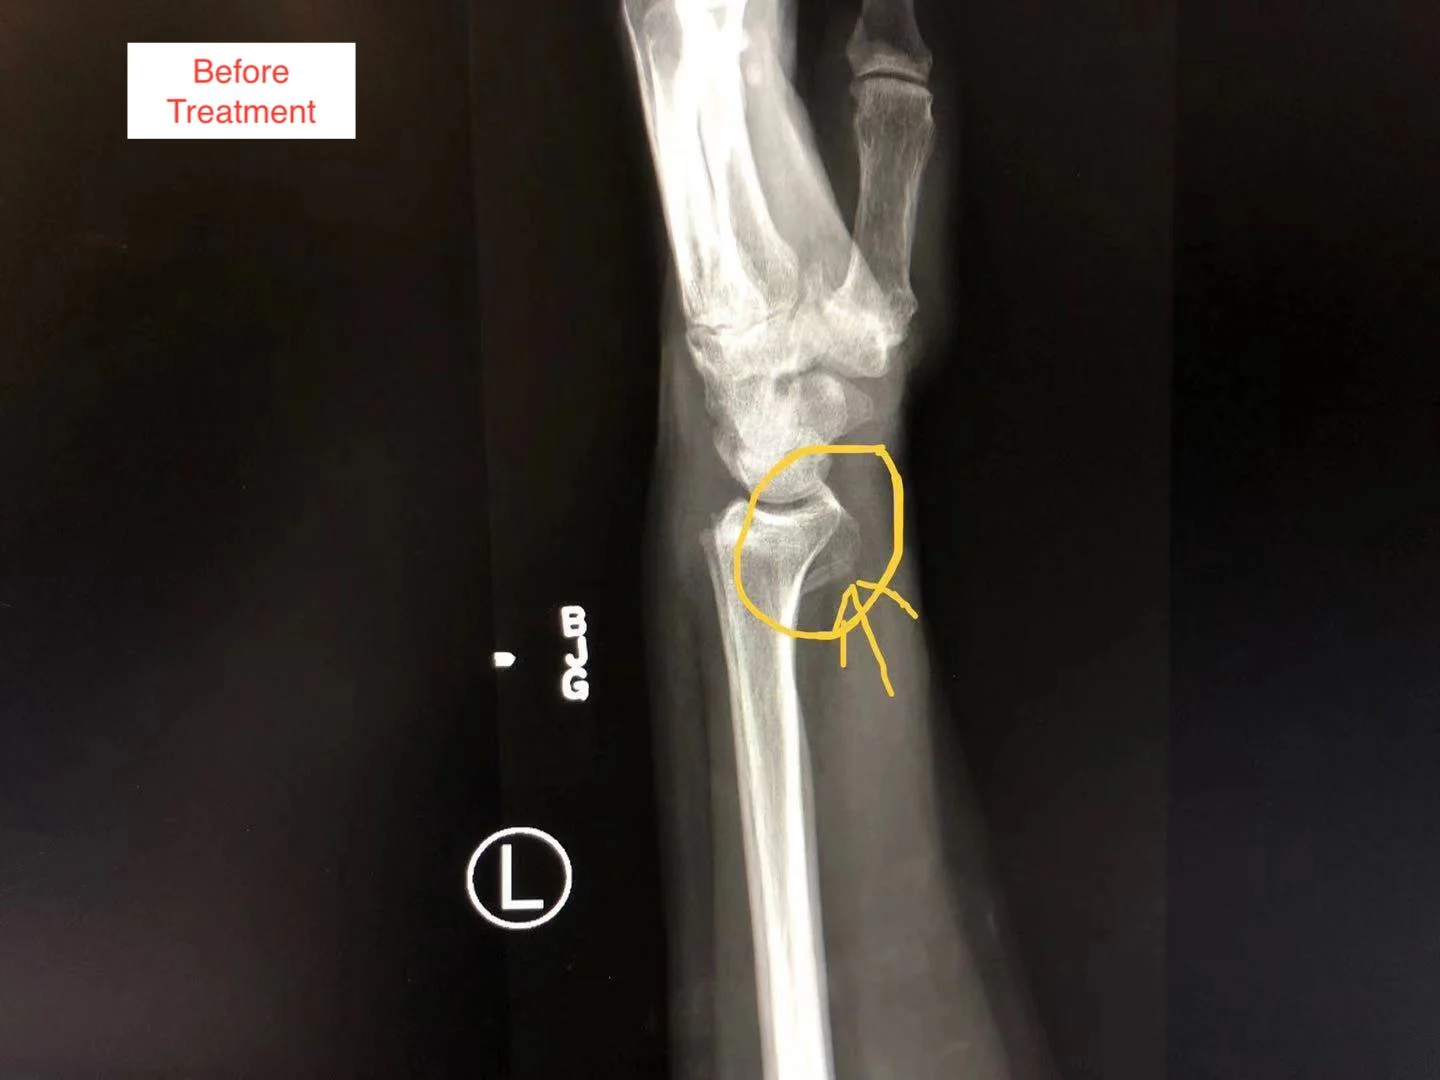

The fracture is Anti Coriolis fracture of the radial bone in the patient’s fore arm.

On this page, you can see the two X-ray pictures from before the treatment, showing the Anti Coriolis fracture of the radial bone. You can also see the X-ray pictures two weeks after the treatment, showing good bone alignment, and normal epiphyseal growth, indicating the clinical healing standard is reached.